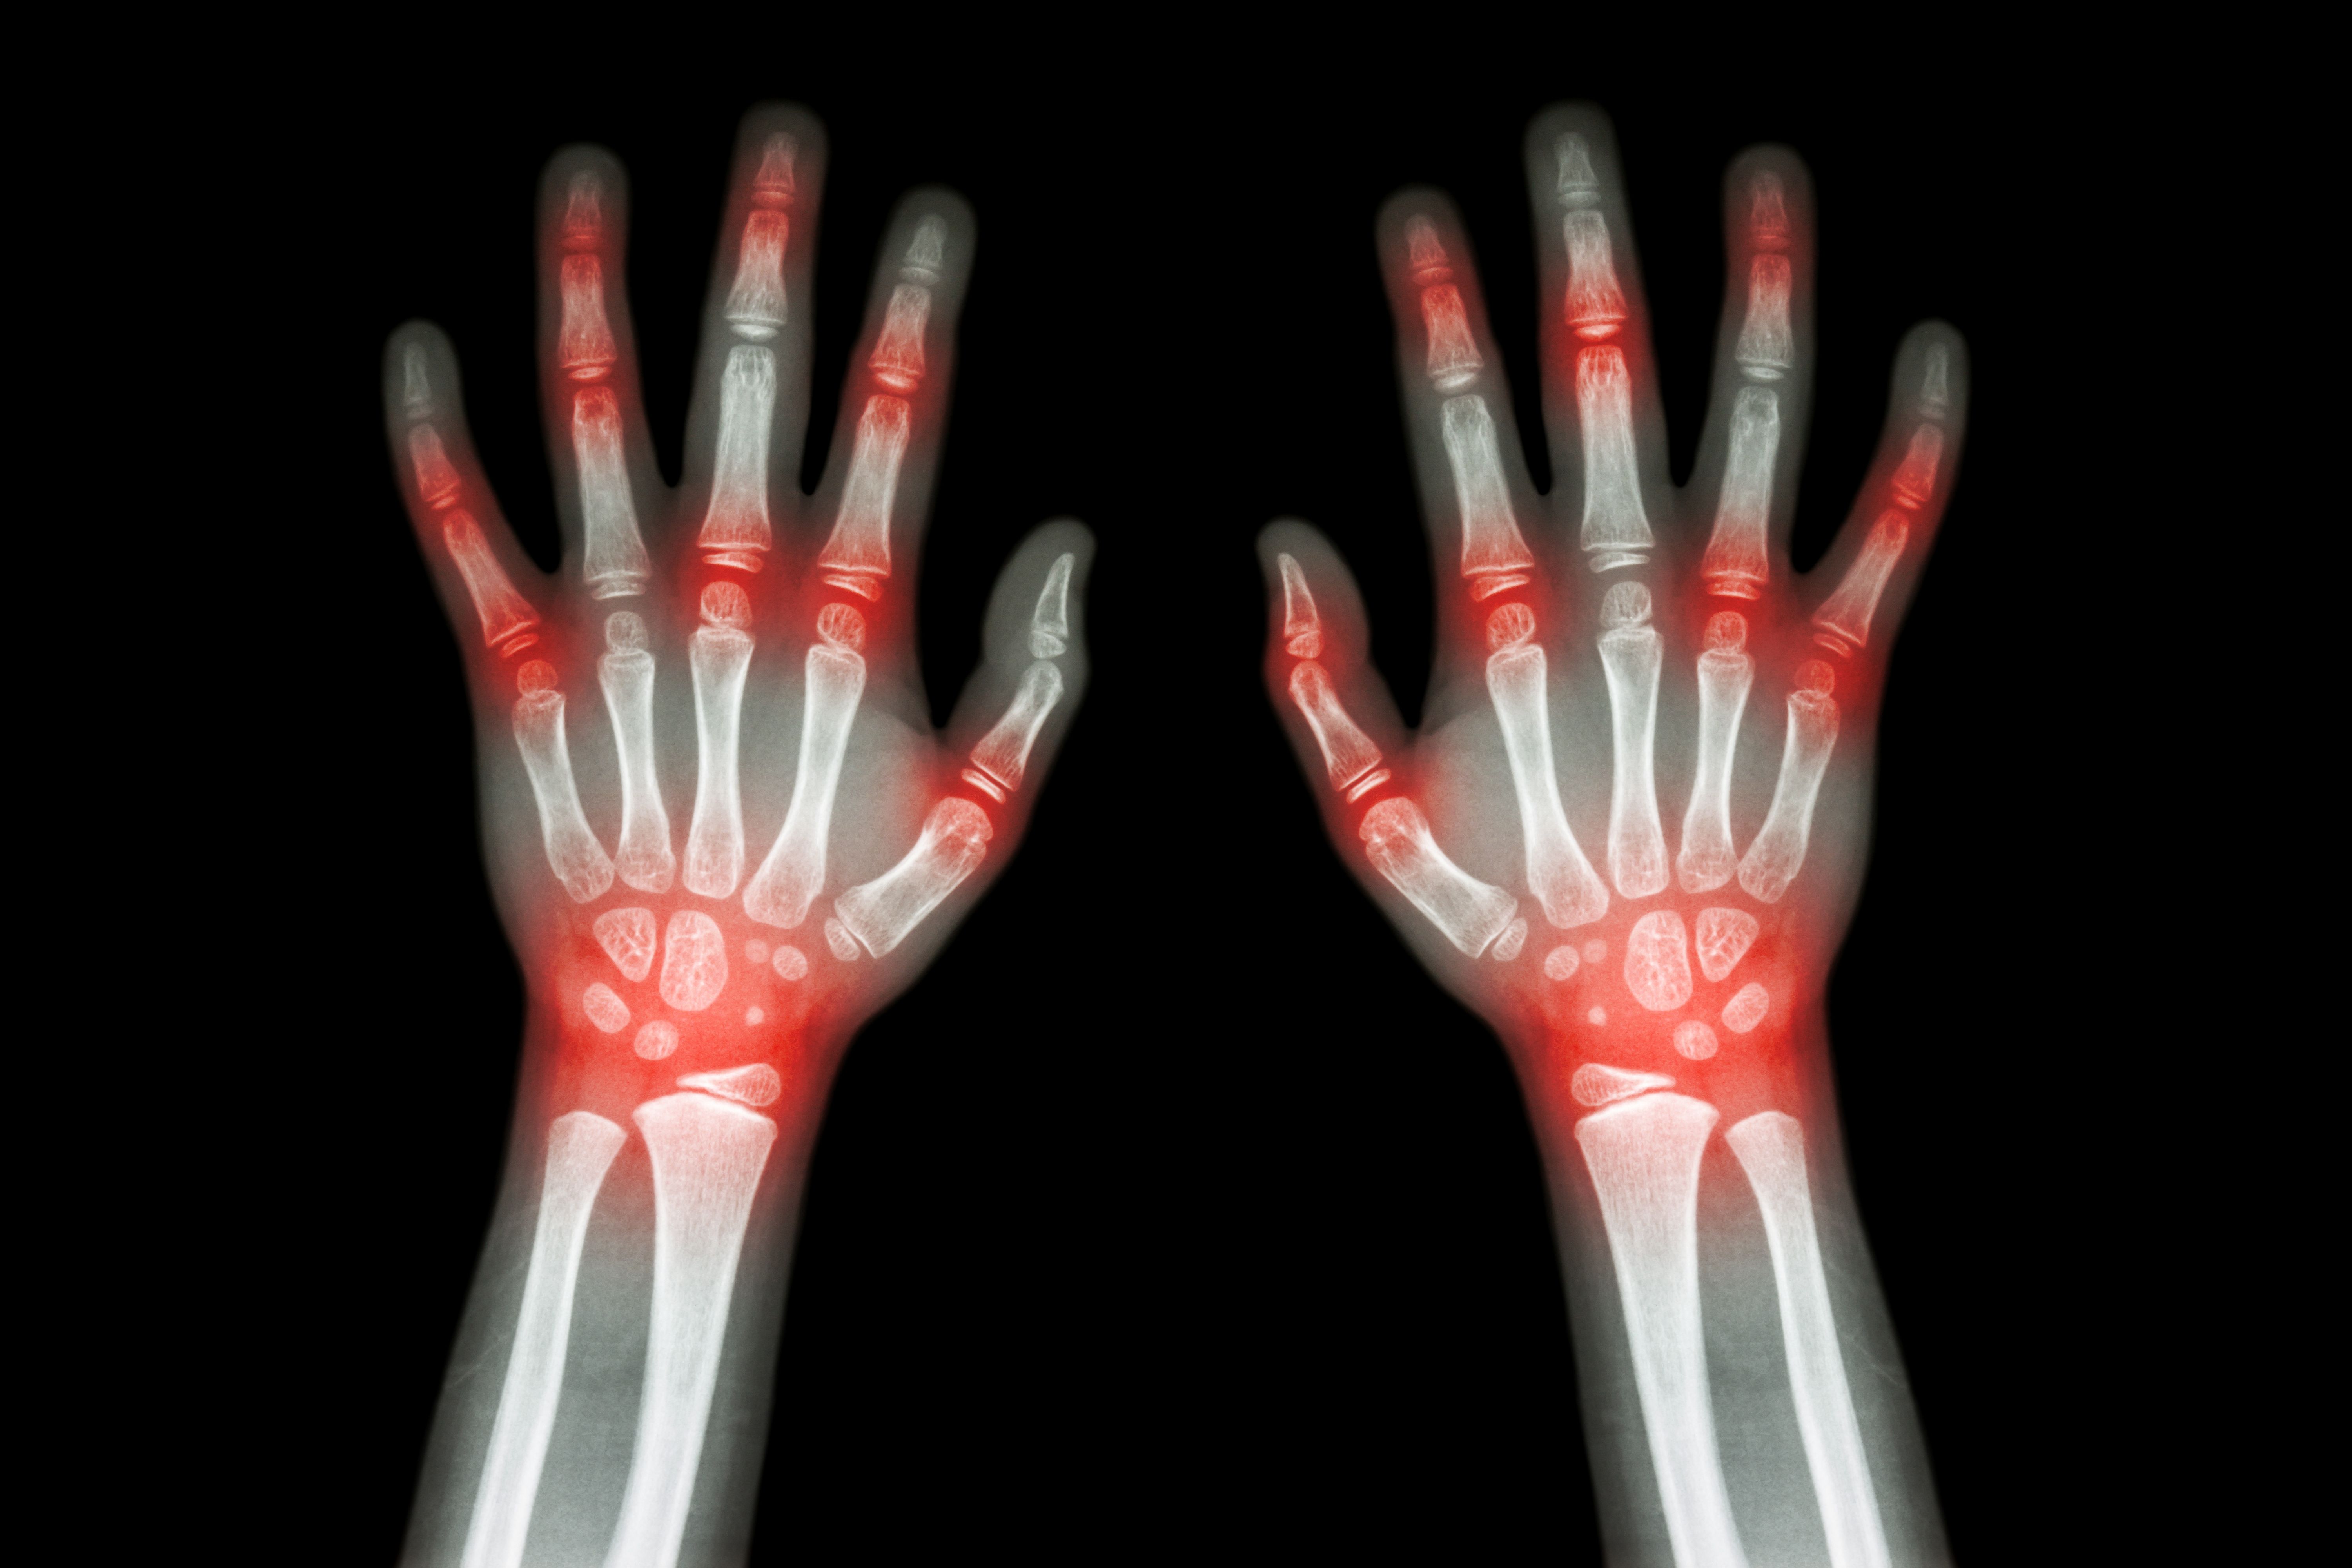

An analysis of perimenopausal women with rheumatoid arthritis indicated that patients receiving exogenous sex hormones more frequently achieved SDAI- and CDAI-defined remission.